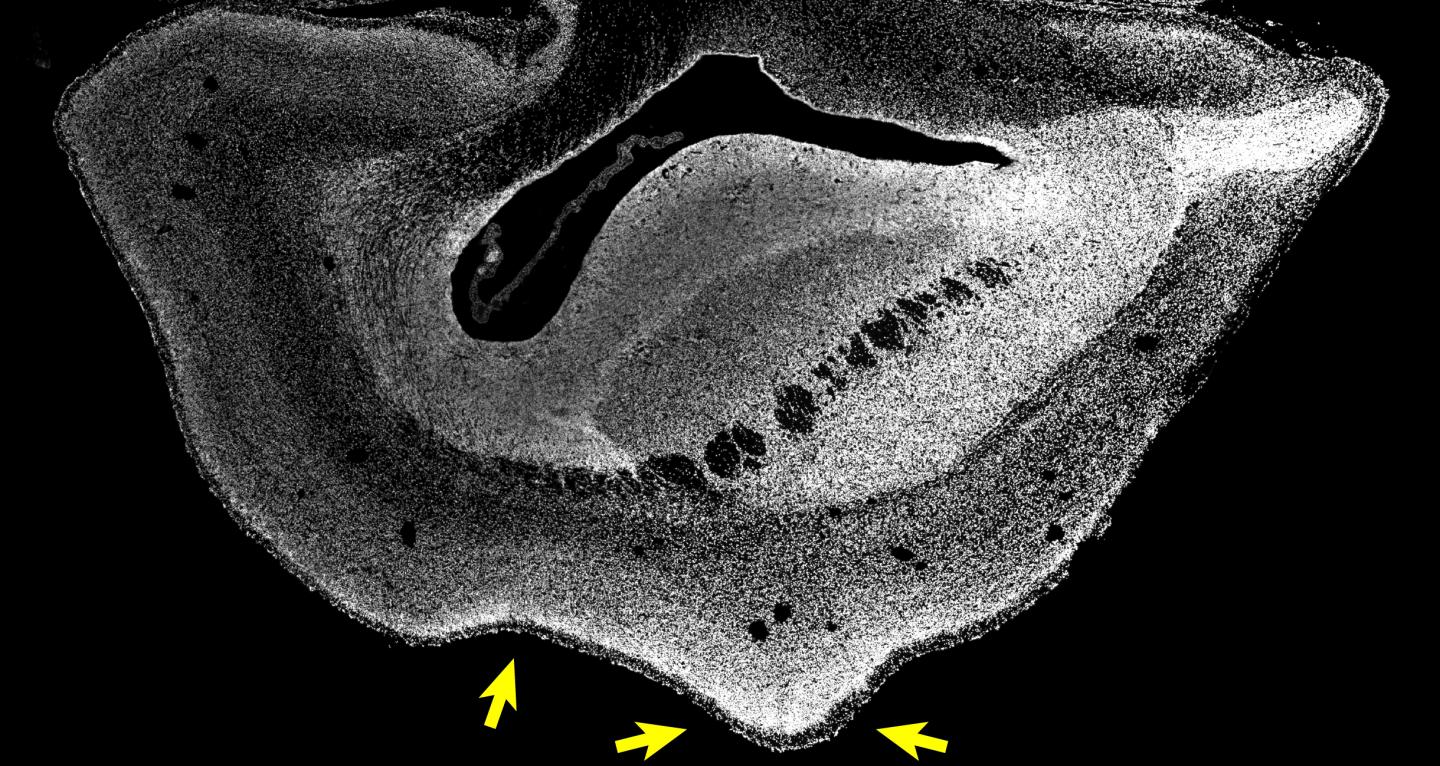

However, it has been unclear until now if the human-specific gene ARHGAP11B would also cause an enlarged neocortex in non-human primates. To investigate this, the researchers in the group of Wieland Huttner teamed up with Erika Sasaki at the Central Institute for Experimental Animals (CIEA) in Kawasaki and Hideyuki Okano at the Keio University in Tokyo, both located in Japan, who had pioneered the development of a technology to generate transgenic non-human primates. The first author of the study, postdoc Michael Heide, travelled to Japan to work with the colleagues directly on-site. They generated transgenic common marmosets, a New World monkey, that expressed the human-specific gene ARHGAP11B, which they normally do not have, in the developing neocortex. Japan has similarly high ethical standards and regulations regarding animal research and animal welfare as Germany does. The brains of 101-day-old common marmoset fetuses (50 days before the normal birth date) were obtained in Japan and exported to the MPI-CBG in Dresden for detailed analysis. Michael Heide explains: "We found indeed that the neocortex of the common marmoset brain was enlarged and the brain surface folded. Its cortical plate was also thicker than normal. Furthermore, we could see increased numbers of basal radial glia progenitors in the outer subventricular zone and increased numbers of upper-layer neurons, the neuron type that increases in primate evolution." The researchers had now functional evidence that ARHGAP11B causes an expansion of the primate neocortex.